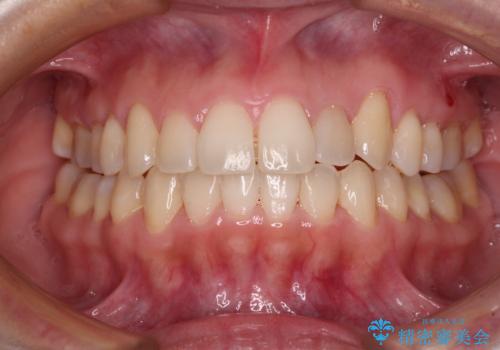

前歯のクロスバイト 目立たないワイヤー装置で矯正治療

- 前歯のクロスバイトを改善したいとのことで来院された患者様です。

マウスピース矯正では前歯の神経への負担が大きいことを懸念され、ワイヤー装置による矯正治療を行うこととしました。

舌の突出癖が認められたため、デコボコ改善に伴い前歯が前突する可能性があったため、舌のトレーニングをしっかりと行うよう指導しながら治療を進めることとしました。

舌の突出癖の影響か、下顎前歯がなかなか整わず、治療期間は予定よりも長期間となりました。

舌突出癖改善のトレーニングの重要性を認識することとなりました。